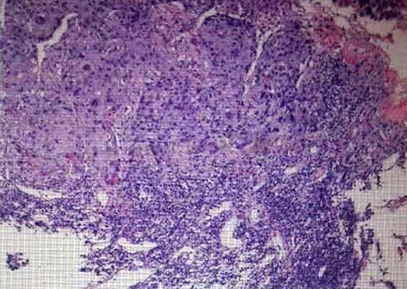

术前胃镜+病理发现食管癌(鳞状细胞癌)